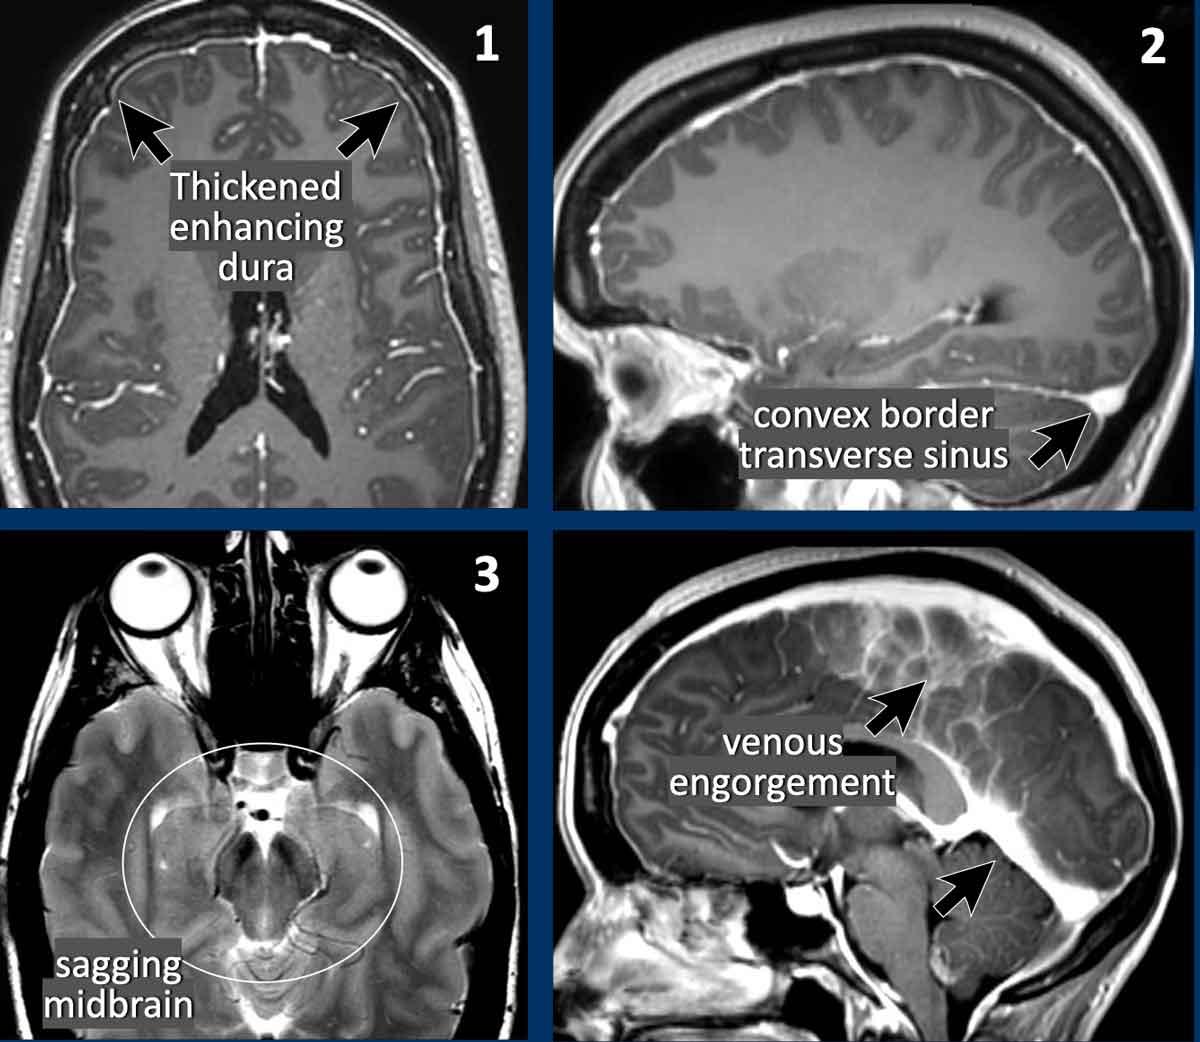

Các dấu hiệu nhạy cảm nhất để chẩn đoán SIH theo thứ tự tần suất gặp là:

- Dày màng cứng có ngấm thuốc (83%).

- Bờ lồi của xoang tĩnh mạch ngang (75%).

- Thân não bị võng xuống (61%).

Dày màng cứng

Dày màng cứng lan tỏa đều đặn đôi khi có thể thấy trên chuỗi xung FLAIR (mũi tên) nhưng dễ nhận thấy hơn trên chuỗi xung T1W sau tiêm thuốc tương phản từ.

Bờ lồi của xoang tĩnh mạch ngang

Trong SIH, bờ dưới của xoang tĩnh mạch ngang có thể có dạng lồi (mũi tên đen).

Trong điều kiện bình thường, xoang tĩnh mạch ngang thường có bờ lõm (mũi tên trắng).

Cơ chế giải thích hiện tượng ứ máu tĩnh mạch và bờ lồi của xoang tĩnh mạch ngang là: thể tích DNT giảm trong hộp sọ ở bệnh nhân SIH được bù trừ bằng sự gia tăng thể tích của các tĩnh mạch não.

Rõ ràng, nhu mô não và các động mạch không thể bù trừ cho sự mất thể tích này, trong khi tổng lượng mô và dịch phải được duy trì không đổi.

Trung não bị võng xuống

Trong các trường hợp SIH nặng hơn, não bị dịch chuyển xuống dưới, dẫn đến thân não bị chèn ép vào nền sọ.

Dấu hiệu này được gọi là “thân não bị trượt xuống” hoặc “trung não bị võng xuống” và được coi là đặc hiệu cho hạ áp nội sọ.

Trong điều kiện bình thường, các thể vú nằm phía trên lưng yên và khoảng cách đến cầu não ít nhất là 5,5 mm.

Khi trung não bị võng xuống, khoảng cách đến cầu não nhỏ hơn 5,5 mm.

Trên các lát cắt axial, sự dịch chuyển xuống dưới của não dẫn đến chèn ép trung não.

Hình ảnh

- Hình ảnh võng xuống với trung não bị chèn ép từ hai phía (vòng tròn).

- Trung não bình thường để so sánh.

Ở bệnh nhân SIH này, tất cả các tĩnh mạch đều giãn và bờ của xoang tĩnh mạch ngang có dạng lồi.

Lưu ý thêm hình ảnh màng cứng dày và ngấm thuốc.